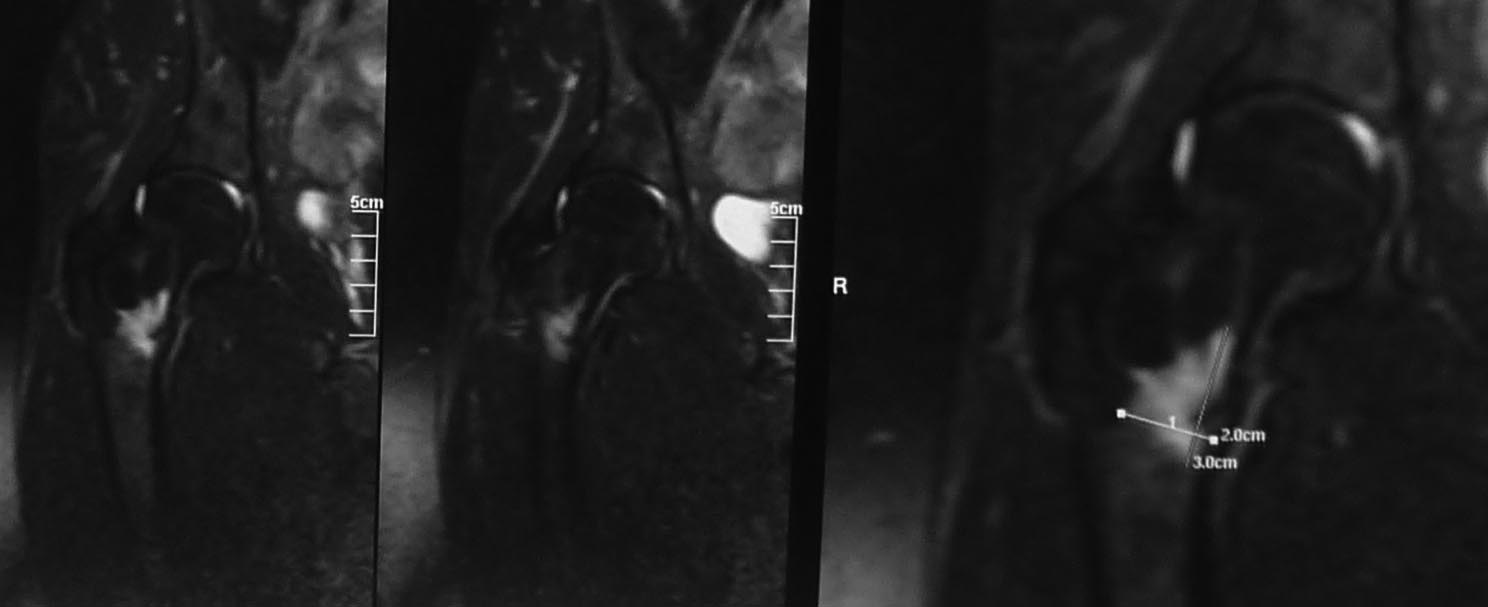

Двухсторонняя патология указывает на стрессовый перелом шейки. По характеру стрессовые переломы разделяются на тензионный в верхнем отделе у пожилых и компрессионнный в медиальной стороне у молодых.

Встречается обычно у бегунов или у активных молодых. МРТ более информативна, чем остальные исследования. Профилактическая перкутанная фиксация винтами поможет уйти от болезненного состояния.

Во вложении похожий случай. Пациентка 50 лет решила подготовиться к любительскому марафону и в течение 2 месяцев бегала 2-3 раза в неделю по нескольку километров. Без предыдущего опыта. Обошлось без операции. Только что вернулась с катания на горных лыжах (через 2 месяца после первичного приема и выполнения МРТ): боли не беспокоят, на консультацию пришла по другому поводу, на компьютерных томограммах изменений нет (поэтому не выкладываю).